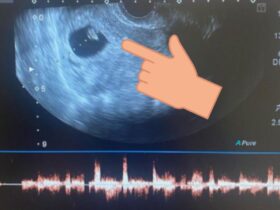

La mala calidad ovocitaria es un tema que afecta a muchas mujeres en todo el mundo, y a menudo se trata de una de las mayores barreras para concebir un hijo. La tristeza, la frustración y la desesperación pueden ser abrumadoras para aquellas que luchan contra este problema, y es importante entender que no estás sola en este camino. Es fácil sentirse desanimada cuando se recibe un diagnóstico de mala calidad ovocitaria, pero es importante recordar que esto no significa que no puedas tener hijos. Con el tratamiento adecuado y una actitud positiva, todavía hay muchas opciones disponibles para ti. En lugar de permitir que la mala calidad ovocitaria te detenga, debes tomar el control de la situación y trabajar junto a los expertos para encontrar el mejor plan de tratamiento para ti. Desde opciones de fertilización in vitro hasta terapias alternativas y cambios en el estilo de vida, hay una variedad de opciones disponibles que pueden ayudarte a lograr tu sueño de tener un hijo. ¿Cómo sé si tengo mala calidad ovocitaria? La mujer inicia la producción de óvulos desde la semana nueve de gestación, conforme avanza el proceso aumenta también la reserva, y para el nacimiento la bebé cuenta aproximadamente con 2 millones de ovocitos. Posteriormente esa reserva de ovocitos baja, y para la pubertad ya quedan alrededor de 400 mil. A partir de esta etapa, la mujer solo producirá entre 350 y 450 óvulos maduros en cada ciclo menstrual, pero la calidad de ellos dependerá de varios factores que van desde los biológicos, hasta los ambientales. Para verificar si este puede ser tu caso, es necesario que siempre lo consultes con un especialista en reproducción, pero es importante que también consideres estos 10 puntos que te permitirán tener un mejor panorama de tu situación en particular. 10 causas de mala calidad ovocitaria: 1. Edad La fertilidad cambia con el paso del tiempo, y este es un elemento distintivo que afecta tanto en cantidad como en la calidad de los óvulos. Esta disminución puede ocurrir mucho antes de lo que la mayoría de las mujeres espera, pero los especialistas sugieren que a partir de los 35 años existe un declive en la fertilidad de la mujer por esta circunstancia. 2. Sobrepeso/Obesidad Además de las múltiples alteraciones en los diferentes sistemas del cuerpo, el sobrepeso y la obesidad también afectan en tu salud reproductiva, específicamente en la calidad de tus óvulos. Así es, está científicamente comprobado que el sobrepeso disminuye considerablemente la cantidad de ovocitos en una punción folicular. Aunado a esto, hay un menor número de óvulos maduros y una baja calidad de ellos que se ve reflejada en menores tasas de embarazo. 3. Tratamientos contra el cáncer Para una mujer que ha pasado por tratamientos de quimio y radioterapia, también influye en la cantidad y calidad de los óvulos, lo que dificulta lograr un bebé en su familia. En este caso, los especialistas recomiendan que antes de iniciar con estos tratamientos, considere congelar sus óvulos y posteriormente iniciar un tratamiento de Reproducción Asistida con mayor tasa de éxito. 4. Causas hormonales Existen desequilibrios hormonales que provocan que la calidad de los óvulos disminuya, o no puedan madurar de manera normal. Uno de los ejemplos más conocidos en este caso es el Síndrome de Ovario Poliquístico. 5. Causas genéticas De acuerdo con los especialistas en Biología de la Reproducción, esta causa es menos frecuente pero es posible, ya que han descrito mutaciones genéticas que provocan rigidez en la zona pelúcida del óvulo. Esta rigidez provoca que sea más difícil de fecundar, o que una vez fecundado, el óvulo no se divida correctamente. 6. Estimulación de la ovulación La estimulación que se utiliza en los ciclos de Reproducción Asistida juega un papel muy importante, ya que el tipo de hormona utilizada y la duración de dicha estimulación pueden influir en la calidad del óvulo. 7. Endometriosis Es un padecimiento que consiste en el crecimiento del tejido que recubre el interior del útero fuera de este, generalmente en las superficies de los órganos u otros lugares donde no se supone que crezca, por ejemplo, en órganos como trompas de Falopio, vejiga y ovarios. La formación de tejido uterino (endometrio) en el ovario, repercute en anomalías en los óvulos. El grado de afectación dependerá de la reserva ovárica, y si hay una mayor reserva entonces incrementa las posibilidades de encontrar óvulos sanos. 8. Alcoholismo Son conocidos los efectos a la salud que provoca el consumo excesivo de alcohol, pero en el ámbito de la fertilidad está científicamente comprobado que su alto consumo disminuye la capacidad para concebir. La Organización Mundial de la Salud (OMS) sugiere que el consumo óptimo de alcohol es de una copa de vino al día para los hombres y la mitad para las mujeres. Sin embargo, si planeas iniciar un tratamiento de Reproducción Asistida, los especialistas recomiendan detener el consumo de alcohol por lo menos de 3 a 6 meses antes de cualquier procedimiento. 9. Tabaquismo ¿Sabías que fumar no solo empeora la calidad de los óvulos, sino que también adelanta la menopausia? Los especialistas han demostrado durante muchos años, que las sustancias que están presentes en el cigarro producen toxicidad en las hormonas implicadas en la ovulación. 10. Problemas inmunológicos Padecimientos como la resistencia a la insulina, hacen que se dificulte el buen funcionamiento del metabolismo y que sustancias como la glucosa, afecten al nivel celular, impactando en la fertilidad. A través de tratamientos de control, los especialistas han demostrado ser efectivos para elevar la calidad de los óvulos y mejorar las tasas de éxito en los tratamientos de Reproducción Asistida. La mala calidad ovocitaria no te impide tener un bebé Conoce la historia de Iraí, quien con un diagnóstico de mala calidad ovocitaria, logró su embarazo y ahora disfruta de al vida junto con su hija Sofía. Si llevas más de un año intentando tener un bebé y no lo has logrado o te diagnosticaron mala calidad ovocitaria, con ayuda de nuestros especialistas, cumpliremos